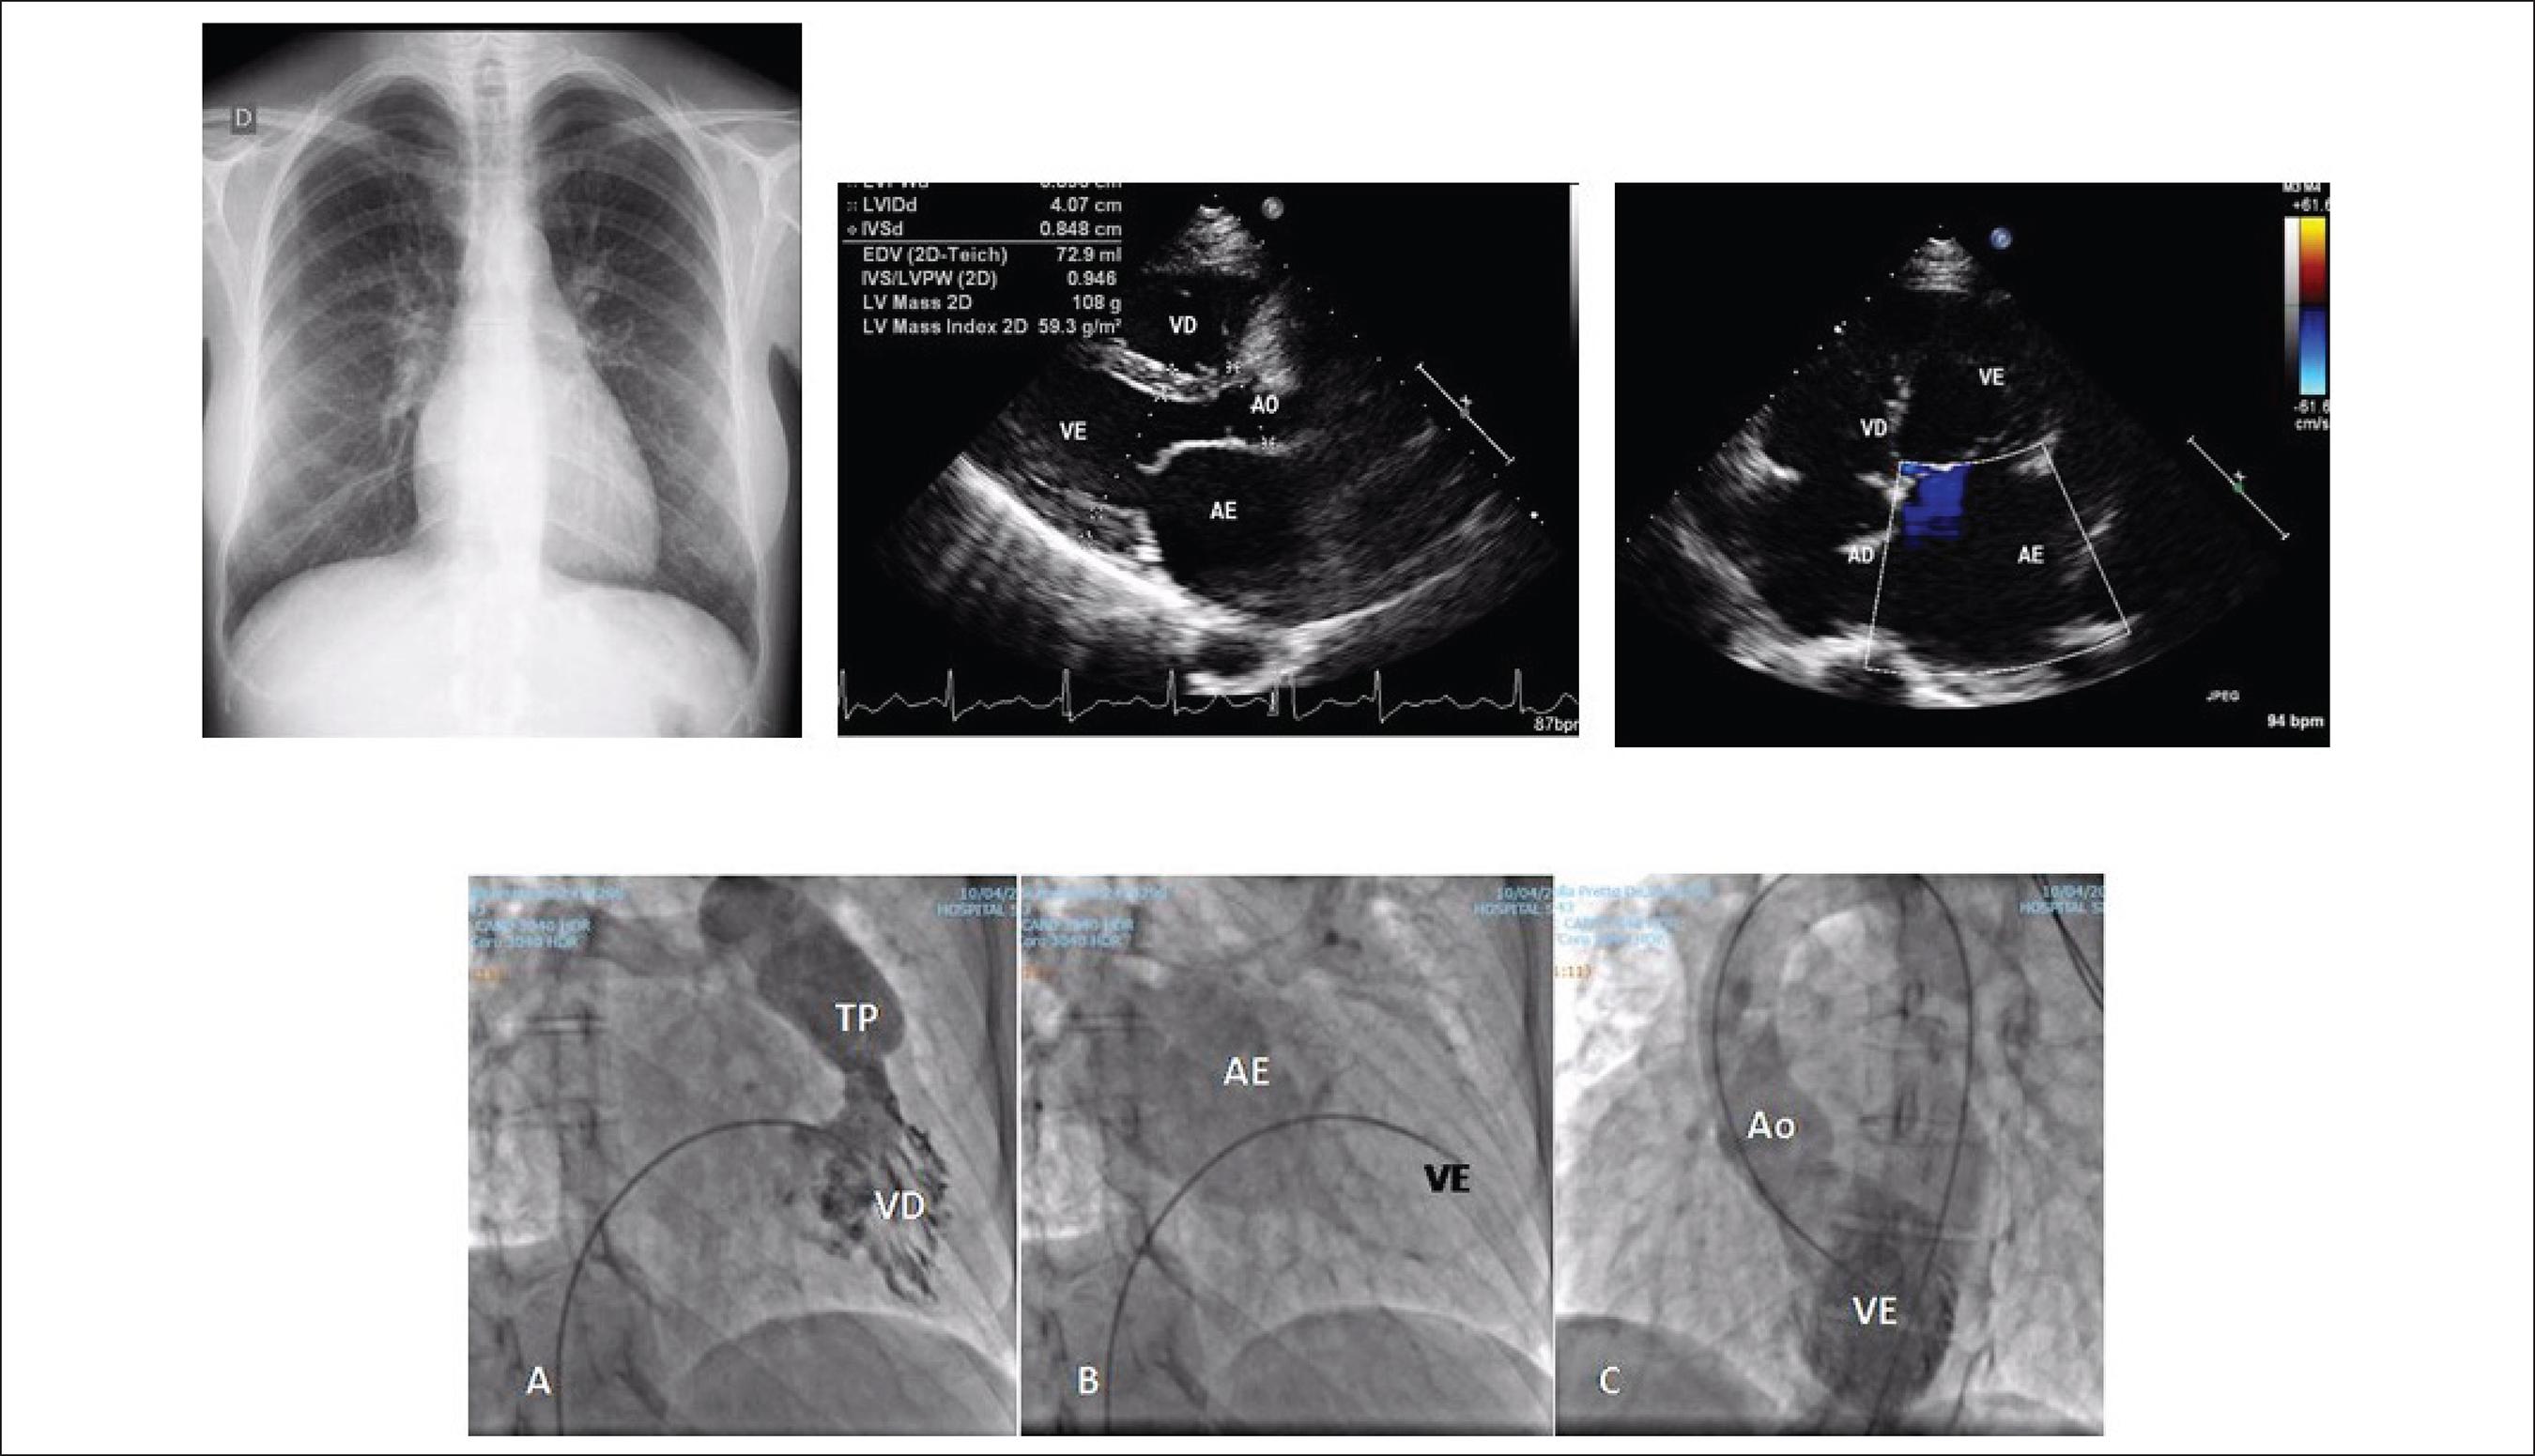

Aplicações práticas do strain no ventrículo esquerdo - Blog Ecope

Weba hipertrofia ventricular esquerda é caracterizada pelo aumento da espessura das paredes do ventrículo esquerdo (parede posterior e/ou septo interventricular), a. Principais doenças dos átrios. Defeitos do septo atrial. O estreitamento da válvula de saída do coração (estenose aórtica) é uma causa importante de sobrecarga de pressão para o. É separado do átrio esquerdo pela válvula mitral e bombeia sangue oxigenado para o corpo através da aorta.

Hipertrofia do ventrículo esquerdo